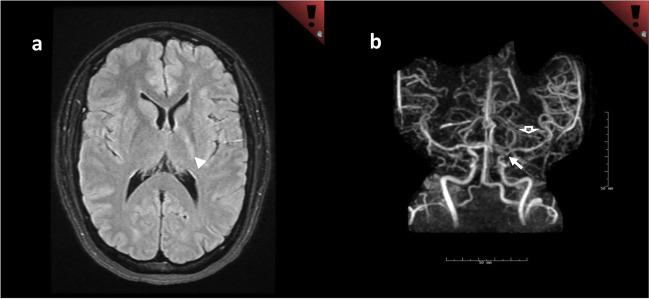

Randomized controlled trials (RCT) on the best medical therapy in the treatment of cervical artery dissection (CeAD) have demonstrated low rates of ischemia with both antiplatelet and vitamin K antagonism. RCT evidence supports the use of anticoagulation with vitamin K antagonism in "high-risk" patients with antiphospholipid antibody syndrome (APLAS), and there is new evidence supporting the utilization of direct oral anticoagulation in malignancy-associated thrombosis. Migraine with aura has been more conclusively linked not only with increased risk of ischemic and hemorrhagic stroke, but also with cardiovascular mortality. Recent literature has surprisingly not provided support the utilization of L-arginine in the treatment of patients with mitochondrial encephalopathy, lactic acidosis, and stroke-like episodes (MELAS); however, there is evidence at this time that support use of enzyme replacement in patients with Fabry disease. Additional triggers for reversible cerebral vasoconstriction syndrome (RCVS) have been identified, such as capsaicin. Imaging of cerebral blood vessel walls utilizing contrast-enhanced MRA is an emerging modality that may ultimately prove to be very useful in the evaluation of patients with uncommon causes of stroke. A plethora of associations between cerebrovascular disease and COVID-19 have been described. Where pertinent, authors provide additional tips and guidance. Less commonly encountered conditions with updates in diagnosis, and management along with clinical tips are reviewed.

关于颈内动脉夹层(CeAD)最佳药物治疗的随机对照试验(RCT)表明,抗血小板和维生素 K 拮抗剂的缺血发生率均较低。RCT 证据支持在抗磷脂抗体综合征(APLAS)的“高危”患者中使用维生素 K 拮抗剂抗凝,并且有新的证据支持在恶性肿瘤相关血栓形成中使用直接口服抗凝剂。有先兆偏头痛不仅与缺血性和出血性卒中风险增加有关,而且与心血管死亡率有关,这一点已得到更明确的证实。最近的文献并没有提供支持使用精氨酸治疗线粒体脑肌病、乳酸酸中毒和卒中样发作(MELAS)患者的证据;然而,目前有证据支持在 Fabry 病患者中使用酶替代治疗。已经确定了可逆性脑血管收缩综合征(RCVS)的其他触发因素,如辣椒素。利用对比增强 MRA 对脑血管壁进行成像,是一种新兴的模式,最终可能在评估不常见卒中病因的患者中非常有用。描述了大量与 COVID-19 相关的脑血管疾病的关联。作者提供了额外的提示和指导,针对与这些关联相关的内容。我们还回顾了一些诊断和管理方面有更新的、不太常见的疾病,并提供了临床提示。